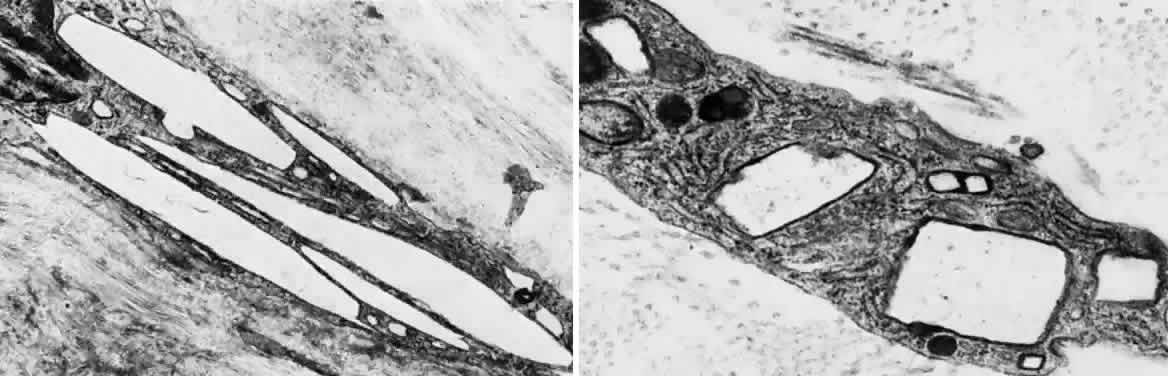

Other ocular findings include whitish conjunctiva, discrete conjunctival plaques, and papillary hypertrophy. Rats fed a diet containing excessive L-tyrosine develop a disease mimicking human corneal disease.18 The corneal lesions in tyrosine-fed rats appear to be caused by the formation and growth of needle-shaped crystals within epithelial cells.19

A current pathogenetic hypothesis involves crystal production in the cornea as a result of a supersaturated state. When crystal formation is initiated in the central cornea, the disruption of cells forms biomicroscopically evident snowflake-like lesions. The crystals exert a force powerful enough to pierce cell membranes and displace nuclei. Lysosomal enzyme release, polymorphonuclear migration, vascularization, and subsequent healing20 follow cell rupture.